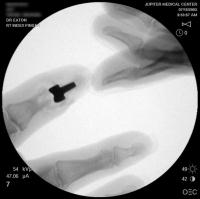

Intraoperative fluoroscopy.

Final implant radiographs.